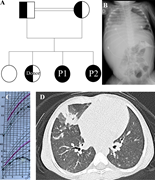

Figure 1. Clinical details of the patients with a pedigree, images and percentiles . (A) Pedigree of the patient family with a homozygous NCKAP1L mutation identified in both affected children P1 and P2. (B) X-ray with massive More about this image found in Clinical details of the patients with a pedigree, images and percentiles ....